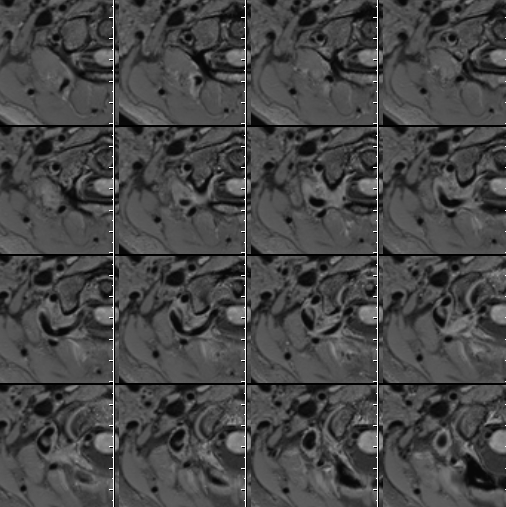

右侧大脑中动脉瘤,右侧椎动脉V2-V3粗细不均伴局部扩张

右侧大脑中动脉瘤,瘤壁强化

右侧椎动脉局部梭形扩张,管壁增厚